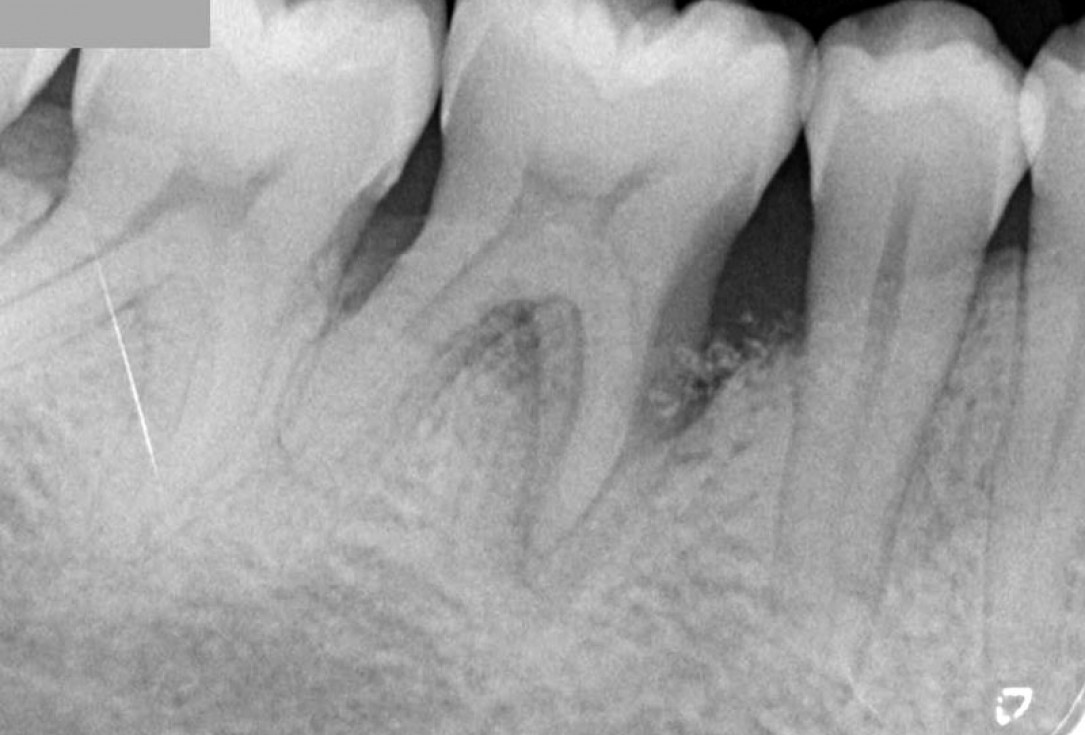

06/08 - Pre-operative radiographRegeneration at LR6 with cerabone® and collprotect® membrane using simple papilla preservation technique - Dr. D. Chatzopoulou